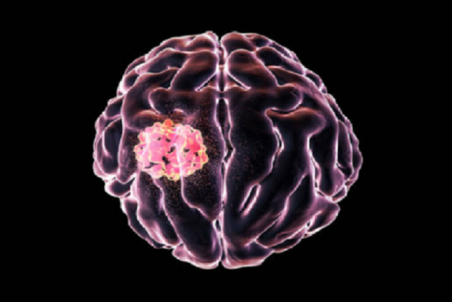

این علائم ساده میتواند نشانه تومور مغزی باشد

در برخی موارد، اسپاسم عضلانی میتواند بهطور متناوب نشاندهنده وجود تومور مغزی باشد و بهطور خاص، اسپاسم عضلانی در ارتباط با تومور مغزی اغلب به شکل انقباض، اسپاسم عضلات یا تشنج است.

روز جهانی تومور مغزی؛ علائم و نشانههای هشداردهنده توده سر

8 ژوئن روز جهانی تومور مغزی است.در این مطلب با توده مغزی، انواع، علائم و عوارض، روش های تشخیص، درمان، خطرات جراحی، پرتو، رادیو و شیمی درمانی آن آشنا خواهید شد.

کدام سردرد نشانه ابتلا به تومور مغزی است؟

متخصصان انگلیسی میگویند اگر سردرد همراه با برخی علائم خاص باشد نشانه ابتلا به تومور مغزی است.

علائم، دلایل، تشخیص و روش درمانی تومور مغزی در کودکان

تومورهای مغزی از شایعترین تومورهایی هستند که کودکان را دچار میکنند و تشخیص زودهنگام آنها میتواند به جراحی موفقتر و درمان نتیجهبخشتری منجر شود. در مطلب زیر در خصوص چیستی، دلایل، علائم و روش درمان تومور مغزی در کودکان صحبت خواهیم کرد.

چگونه ابتلای خود به تومور مغزی را تشخیص دهیم؟

تومور مغزی با عنوان رشد سلولهای مغز که به طور غیرطبیعی تکثیر مییابند، تعریف میشوند.

سومین سرطان شایع کودکان/ علائم تومور مغزی در بچه ها

اگر چه تومور مغزی کودکان سومین سرطان شایع در بچه ها است، ولی به دلیل عدم آشنایی والدین با علائم این بیماری، اغلب زمانی به پزشک مراجعه می کنند که تومور به مرحله پیشرفته رسیده است.